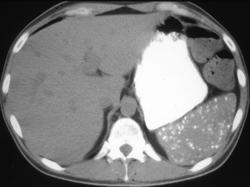

Thorotrast in Spleen